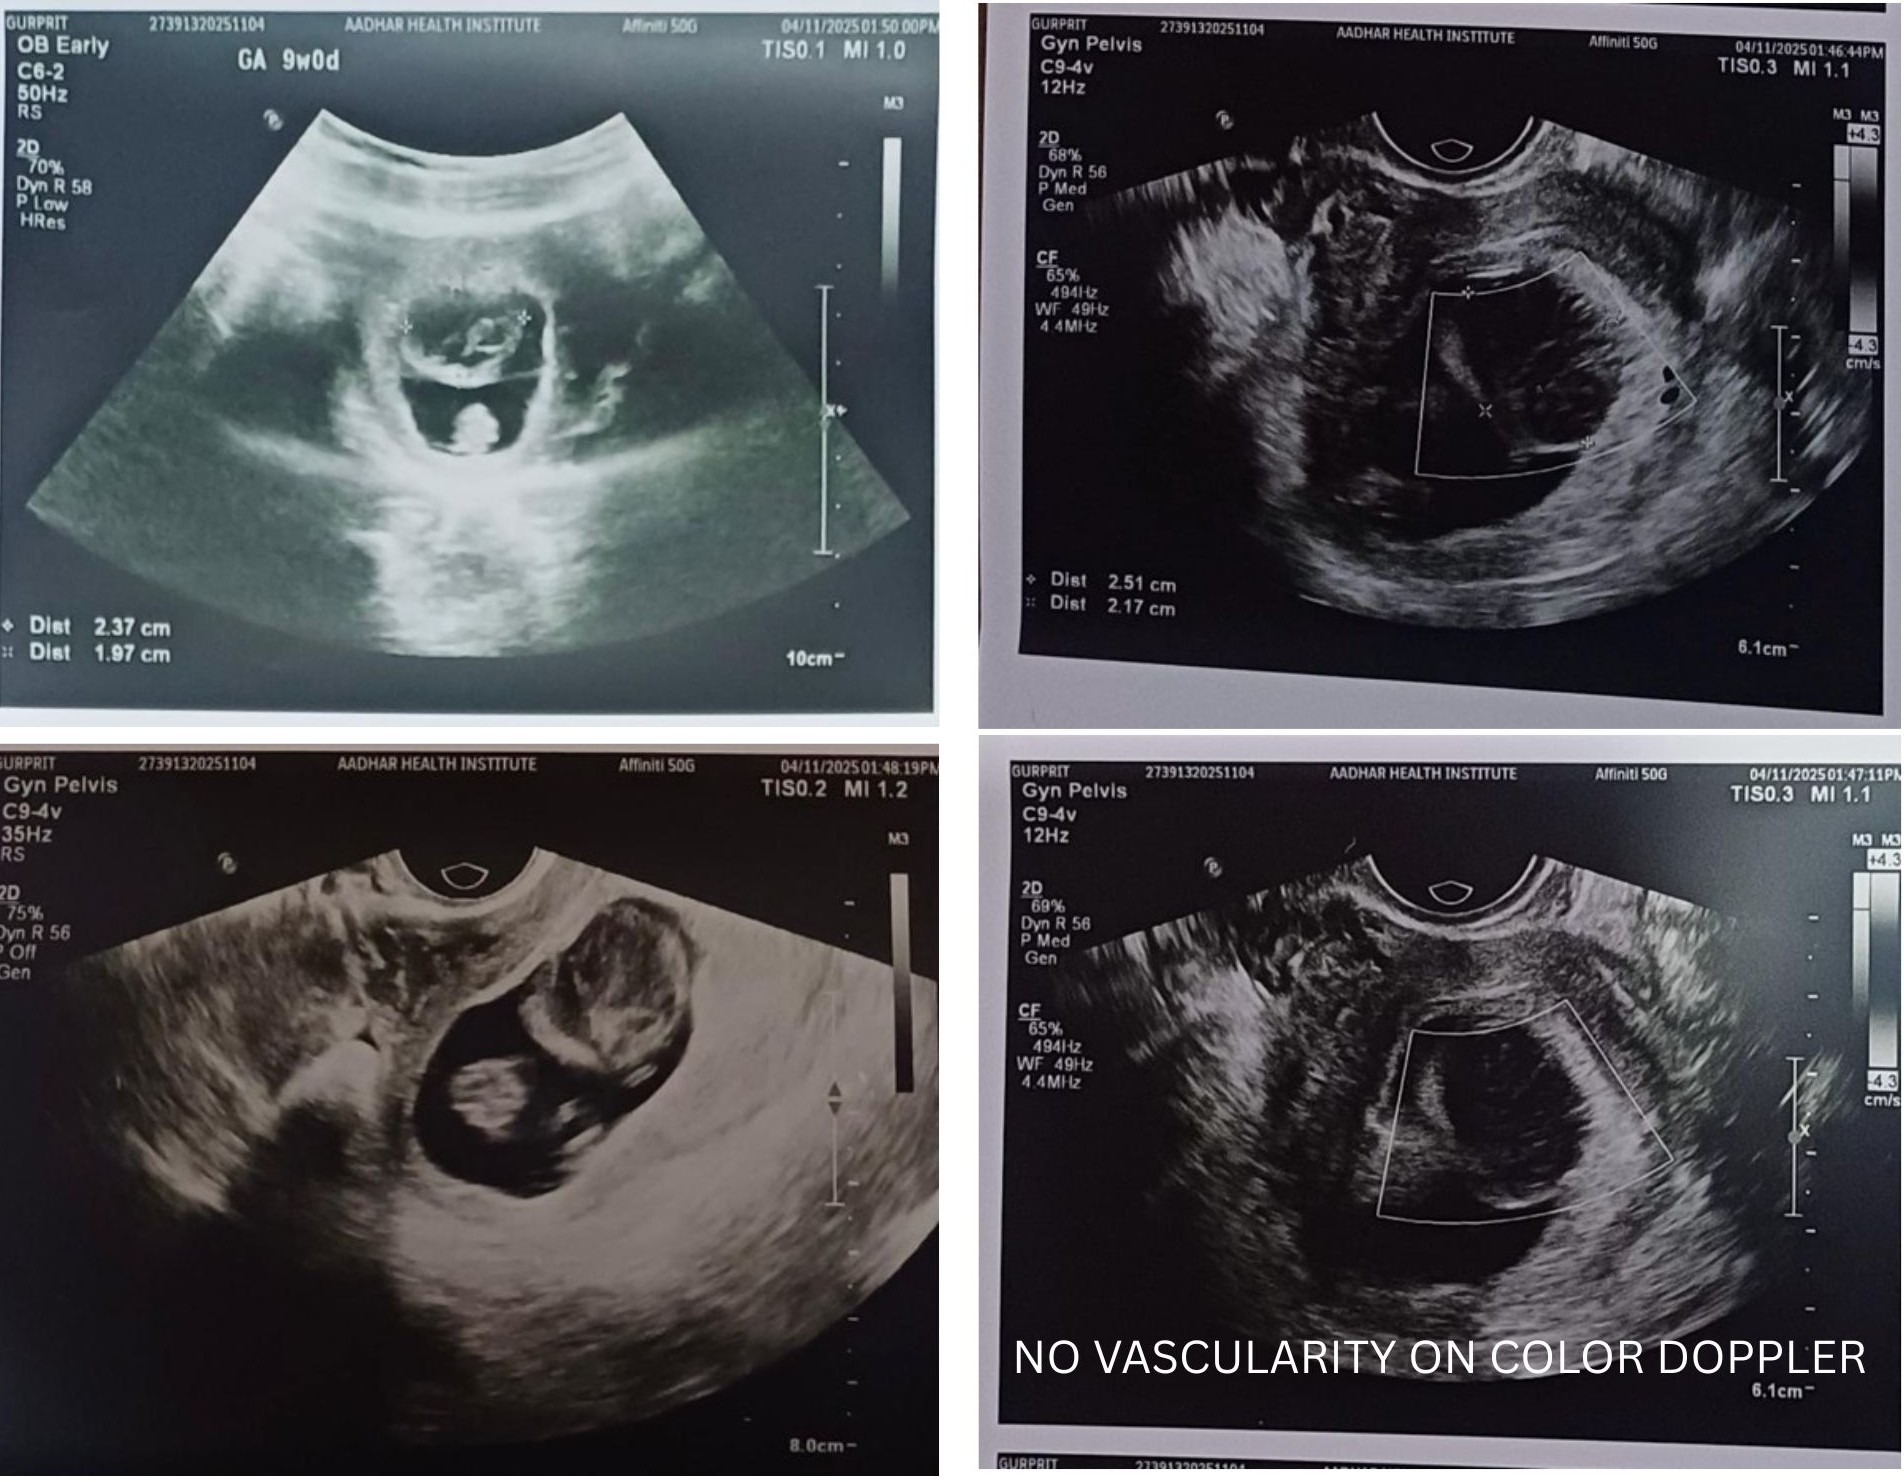

A 28-year-old female presented for a routine early pregnancy ultrasound at 9 weeks of gestation.

USG Images

Ultrasound Findings

Single live intrauterine pregnancy

Cardiac activity present

A well-marginated heteroechoic lesion projecting into the gestational sac from the chorionic wall

No internal vascularity on Color Doppler

No subchorionic hematoma or free fluid